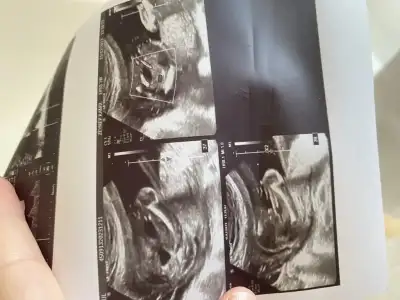

Banda bakarmisiniz lütfen 11+5

cinsiyeti nedir acaba?cıkıntı düz gliyosa kız yukarı bakıyosa erkek oluyor sizinki kıza benziyor :)

Merhaba cinsiyetiniz nedirArkadaslar 10 hafta 3 gunluk hamileyim ultrason fotografima gore cinsiyet tahmin edenler varmi

kız gibi geldi bana :)Tahminleri alalımsizce ne

yukardaki cıkıntı benide dusundurdu ama o kdar uzun olurmu ya kac haftalıkYaaçıkıntı ne o zaman

çoğu kişi erkek dedi ama bekleyip göreceğiz teşekkürler

Olabiliryukardaki cıkıntı benide dusundurdu ama o kdar uzun olurmu ya kac haftalıkbszı durumlarda göbek bagıylada karstırılıyor

13+1 haftalıkyukardaki cıkıntı benide dusundurdu ama o kdar uzun olurmu ya kac haftalıkbszı durumlarda göbek bagıylada karstırılıyor